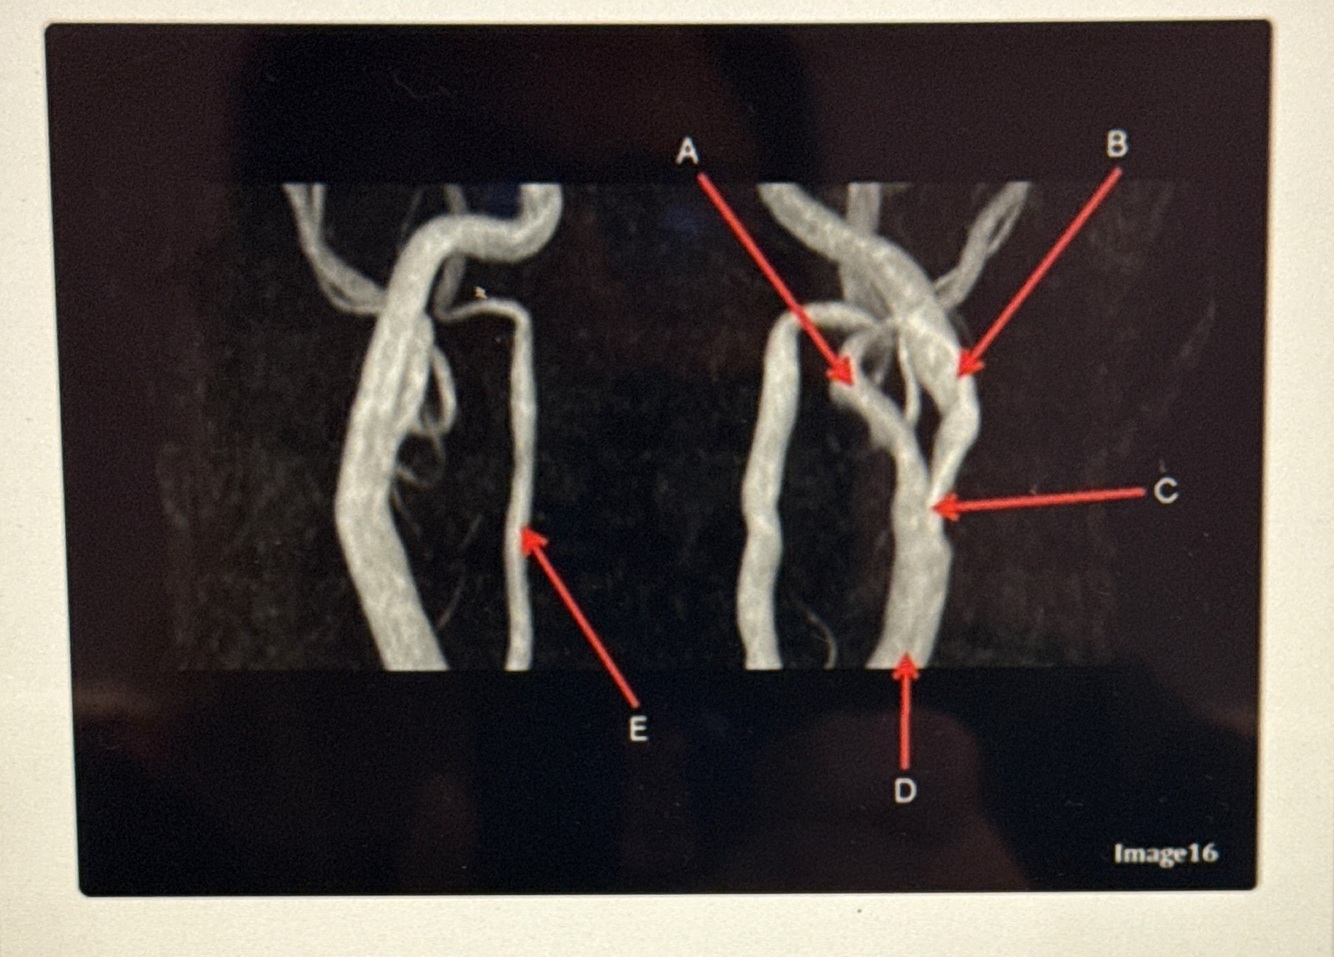

Q

What kind of MR image

A

MRA EXTRACRANIAL CIRCULATION

Letter A points to the

VertebroBasilar junction

Letter B points to the _______ and letter D points to the ______

B. External carotid artery

D. Vertebral artery